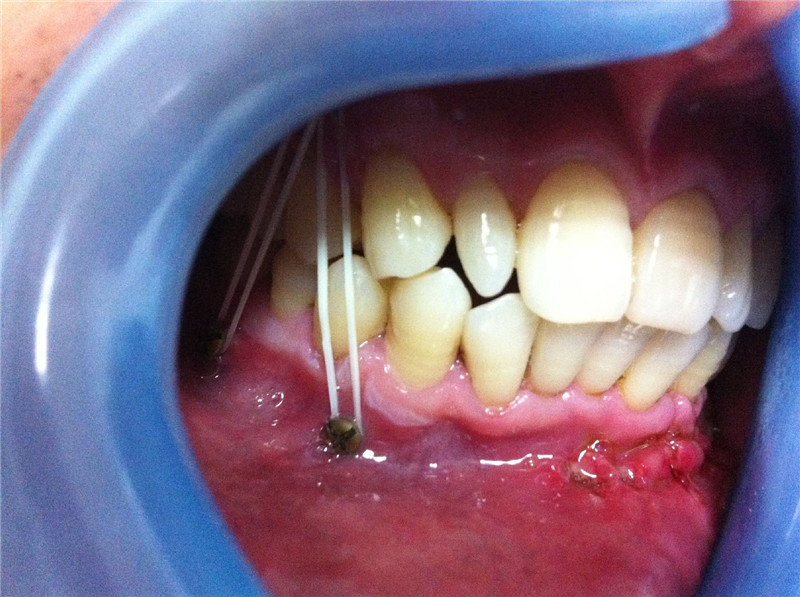

颌面部骨折导致的面容及咬合关系的改变

坚强内固定联合变化的颌间牵引保证术中以及术后咬颌关系的恢复